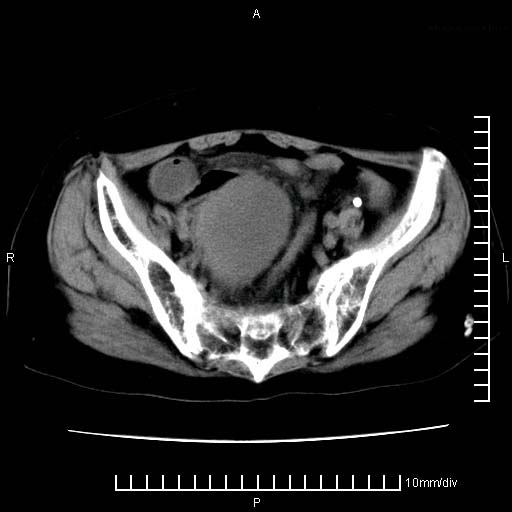

标题: CT24821:女性,70岁

下腹疼痛2月,加重并呕吐2天,下腹压痛,反跳痛。白细胞1万2.

下腹至盆腔较大包块,与邻近肠管关系密切,下腹疼痛2月,加重并呕吐2天,下腹压痛,反跳痛。白细胞1万2.

由于没有做肠道准备很难分清是哪根肠管,但看位置考虑为升结肠回盲部的问题,我首先考虑化脓性阑尾炎,不除外结肠癌合并感染化脓。建议做增强进一步明确。

补充:道格拉斯腔内有积液,且密度较高,显然提示有感染。

考虑右侧卵巢囊肿伴感染可能性大。

附件实性肿块有坏死 考虑卵巢癌

来源于附件占位—多考虑:卵巢癌!